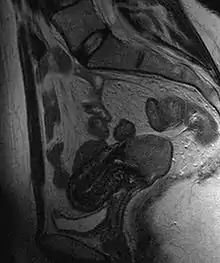

Often before the biopsy, the doctor asks for medical imaging to rule out other causes of woman's symptoms. Imaging modalities such as ultrasound, CT scan, and MRI have been used to look for alternating disease, spread of the tumor, and effect on adjacent structures. Typically, they appear as heterogeneous mass on the cervix.[47]